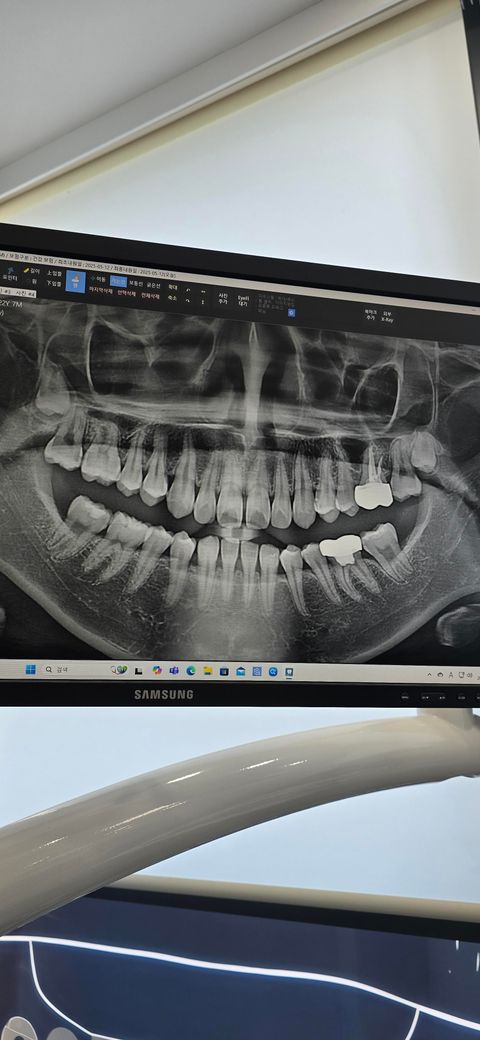

인접면충치 정지우식 될 가능성이 있나요

크라운 씌운 어금니 쪽에 충치2개와

왼쪽 위 어금니 충치하나 관리 잘하면 정지우식이 될까요

그리고 아래 인접면 충치는 신경을 침범하지. 않았는데 음식을 먹을 때 통증이 있는데 왜 그런가요

• 1번 째 사진